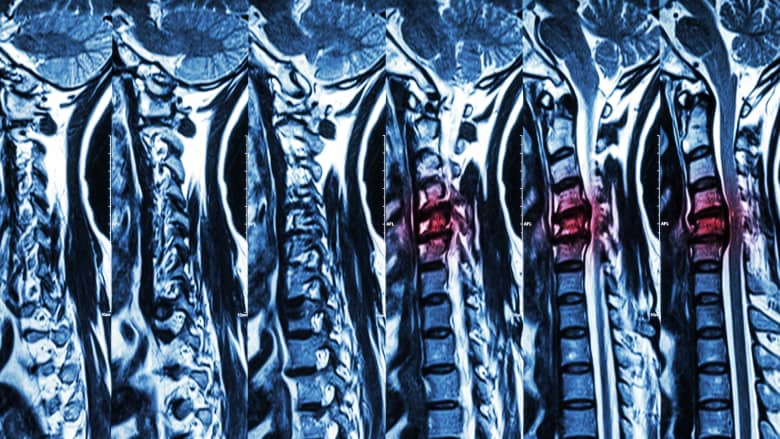

Magnetic resonance imaging (MRI) is used when high-resolution images of the body’s tissues are required for diagnosis and treatment.

For back or neck pain, MRI scans are a preferred diagnostic tool for investigating musculoskeletal problems with or without neurologic deficits when previous imaging is suggestive of spinal pathology. However, the presence of certain implants or prostheses may interfere with the MRI process, making it a health risk.

Severe spinal cord compression is evaluated in detail on an MRI scan.